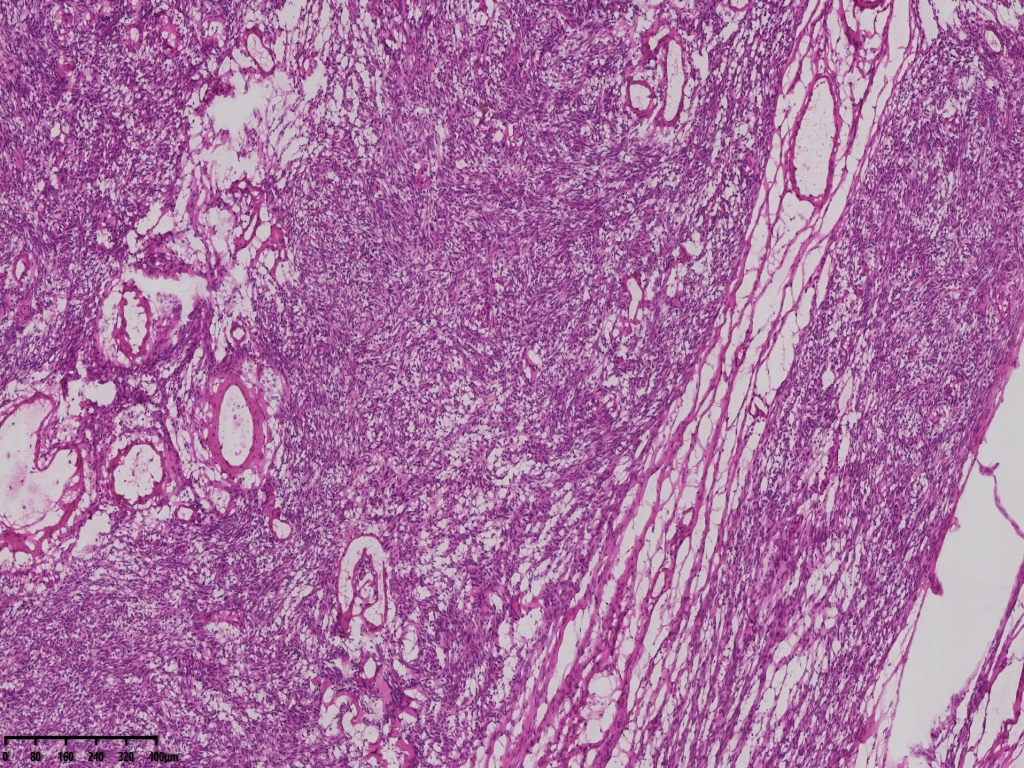

冰冻切片取两块实性区组织,其中1块可见梭形细胞为主,另一块似上皮样细胞,细胞丰富密集。

术中考虑卵巢性索间质来源肿瘤,待石蜡及免疫组化。

考虑颗粒细胞瘤。